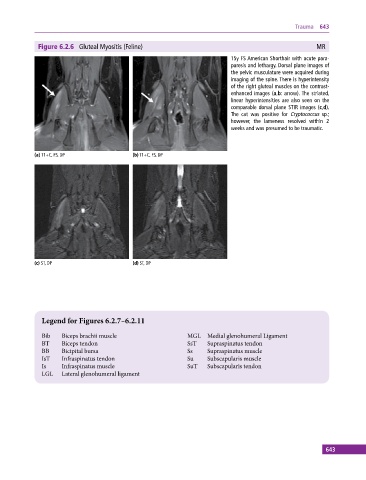

Figure 6.2.6 Gluteal Myositis (Feline) MR

15y FS American Shorthair with acute para-

paresis and lethargy. Dorsal plane images of

the pelvic musculature were acquired during

imaging of the spine. There is hyperintensity

of the right gluteal muscles on the contrast‐

enhanced images (a,b: arrow). The striated,

linear hyperintensities are also seen on the

comparable dorsal plane STIR images (c,d).

The cat was positive for Cryptococcus sp.;

however, the lameness resolved within 2

weeks and was presumed to be traumatic.

(a) T1+C, FS, DP (b) T1+C, FS, DP

(c) ST, DP (d) ST, DP